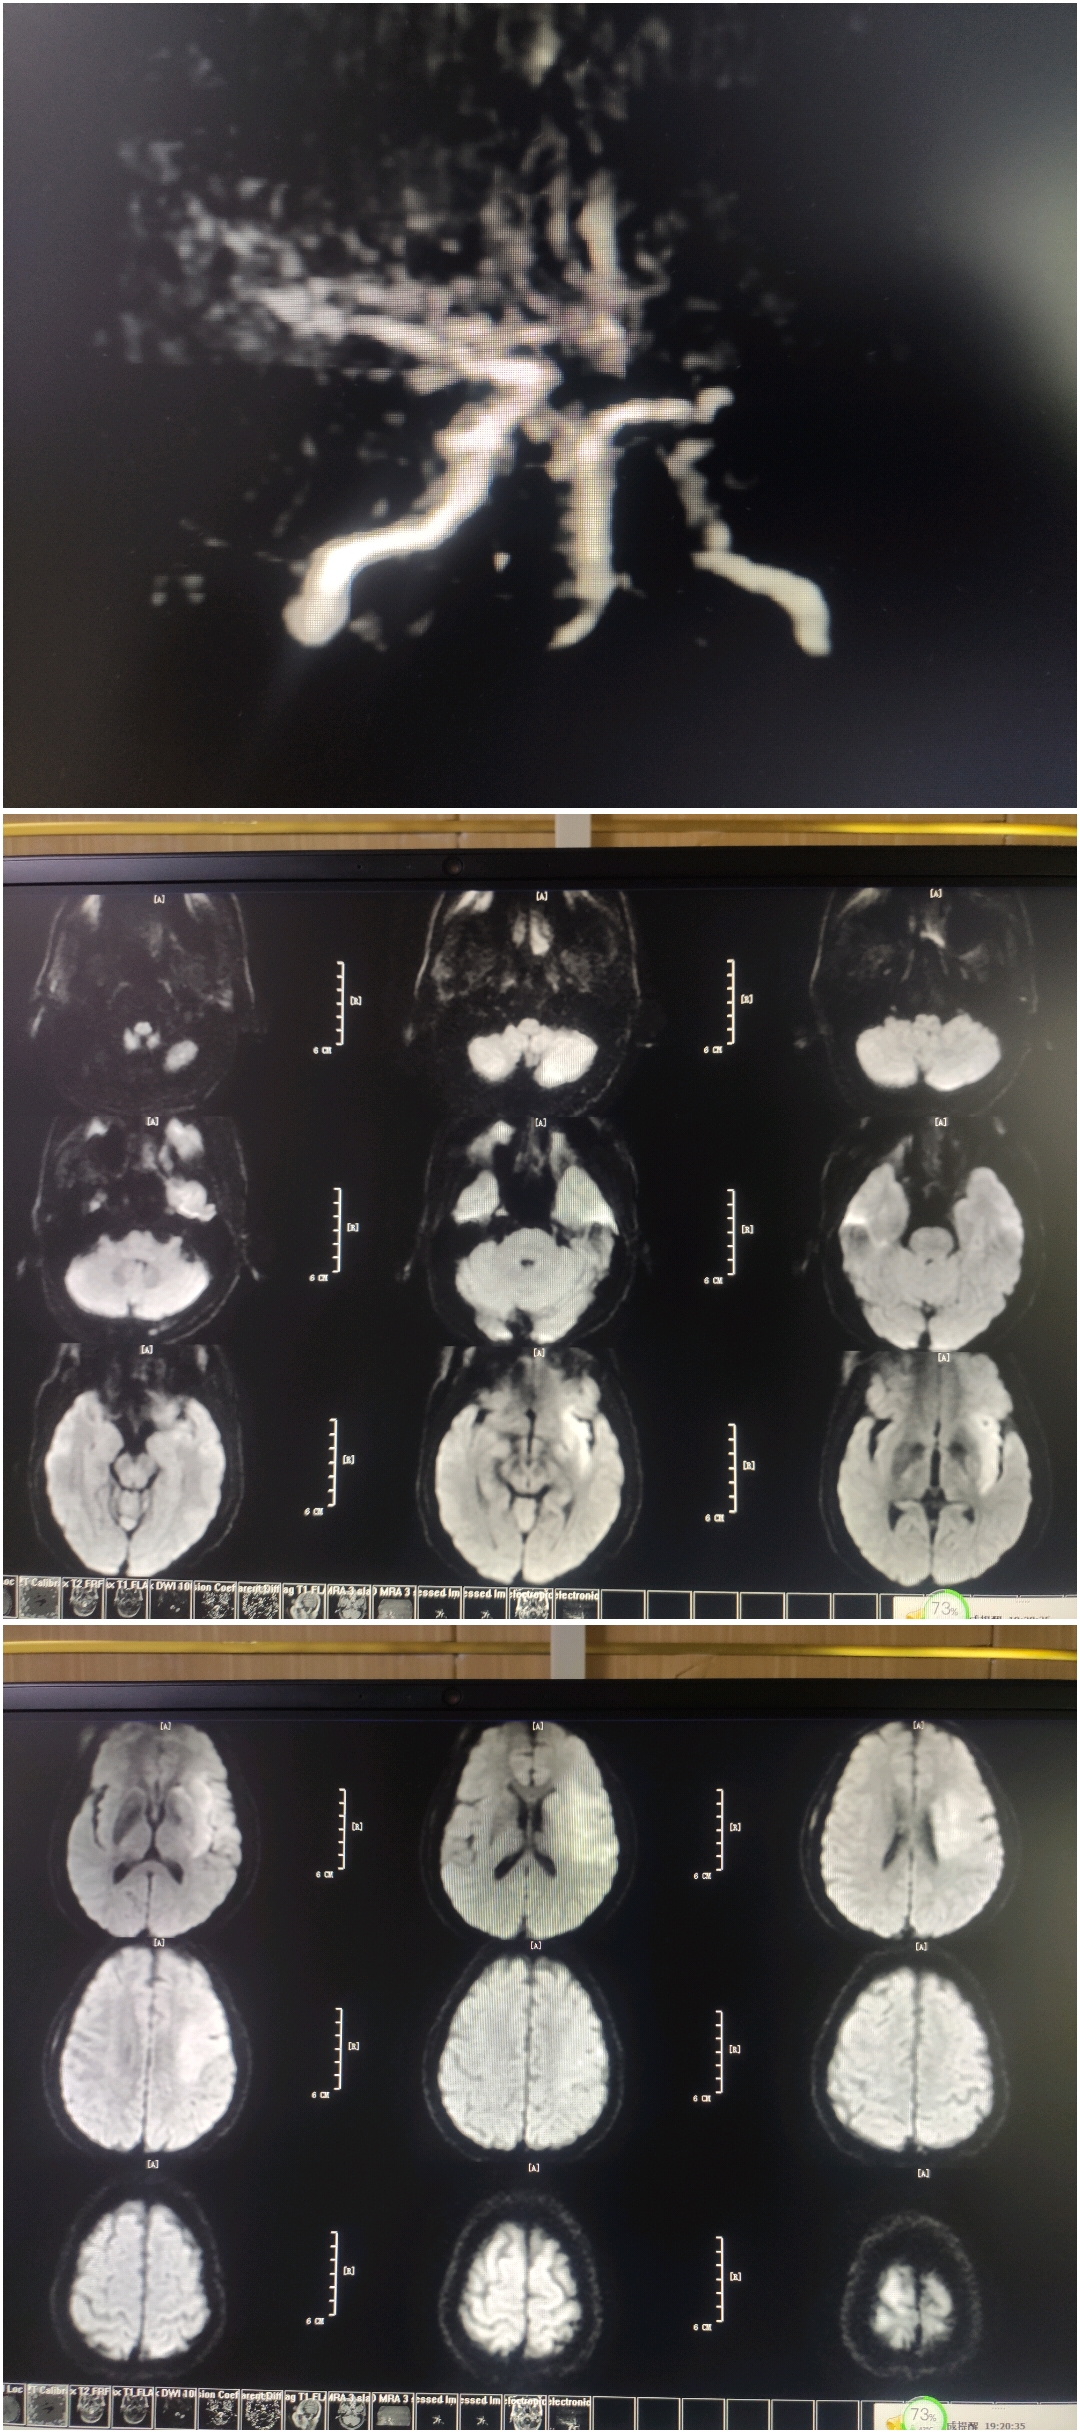

MRA提示:左侧颈内动脉末端及左侧大脑中动脉未见显影。DWI提示左侧大脑中动脉供血区高信号。DWI-Aspect评分:4分。醒后卒中,DWI信号不高,考虑存在大体积缺血半暗带,急诊血管内治疗。

1.正常可以用取栓支架拉一把,但患者醒后卒中,无房颤病史,梗死位于基底节,皮层部分幸免,考虑有代偿,推测为ICAS闭塞,闭塞近段闭塞形态,以及远端微导管造影,更加确定ICAS。所以没有拉栓,而采用直接球囊扩张。